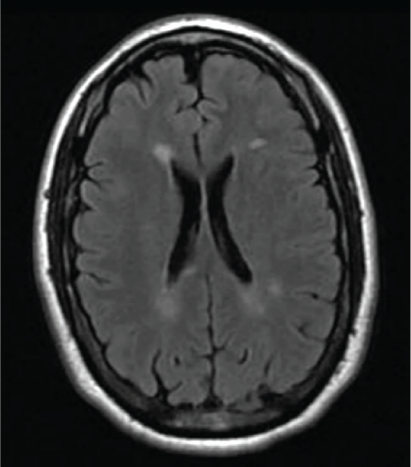

A complete neurologic history was obtained, confirming multiple previous demyelinating events. Neurologic examination was notable for residual right internuclear ophthalmoplegia and central scotoma, without weakness, sensory deficits, or ataxia. Brain magnetic resonance imaging (MRI) before fingolimod discontinuation demonstrated multiple ovoid, periventricular, and cortical/juxtacortical lesions, including at least one new lesion (Figure 2 and Figure S1, which is published in the online version of this article at ijmsc.org).

Brain magnetic resonance image at diagnosis of pulmonary cryptococcosis